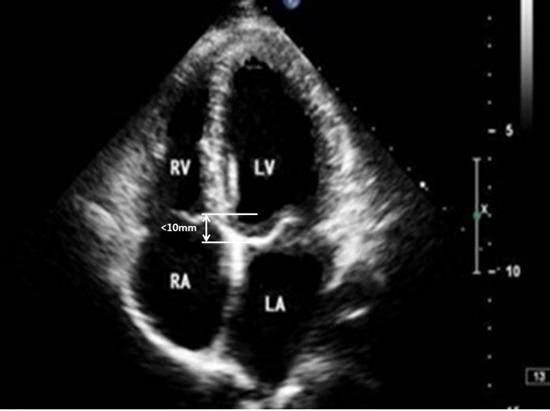

心尖四腔心切面示意图

心尖四腔心切面示意图,心尖五腔心切面示意图

心尖四腔心切面(上)